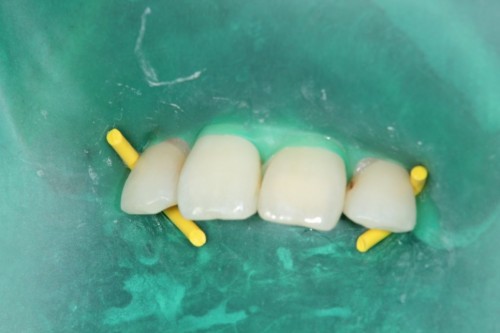

前歯の虫歯です。唾液の量が多い方や歯ぐきから出血がある方にはラバーダム防湿法を使います。このように緑色のゴムのシートを使用して、歯に唾液や血液が付かない様にします。

虫歯をとったところです。

無事治療が終わりました。削った穴に唾液や血液が入り込むと接着力が低下してしまいます。今回、削った穴に汚れが付く事無く、審美的な治療が出来ました。

ダイレクトボンディング

費用2万円×2本

リスクとして変色や欠ける可能性がある(修復可能)。